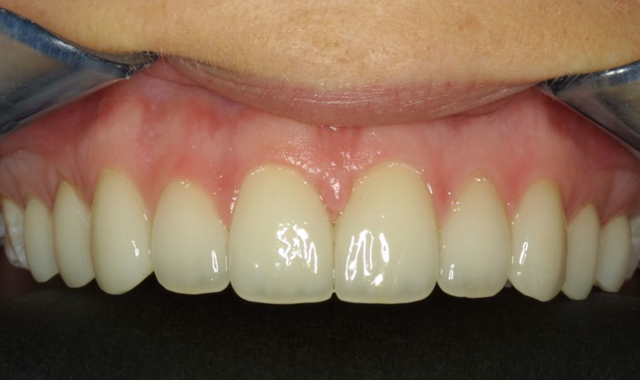

Here is a case where the tissue has been recontoured before veneer preparation (Fig. 5), and during this same appointment the equi-gingival veneer preparations were finished and impressions were done. A few weeks later the veneers were placed and Figure 6 shows the predictability in tissue position.

Fig. 5 Fig. 6